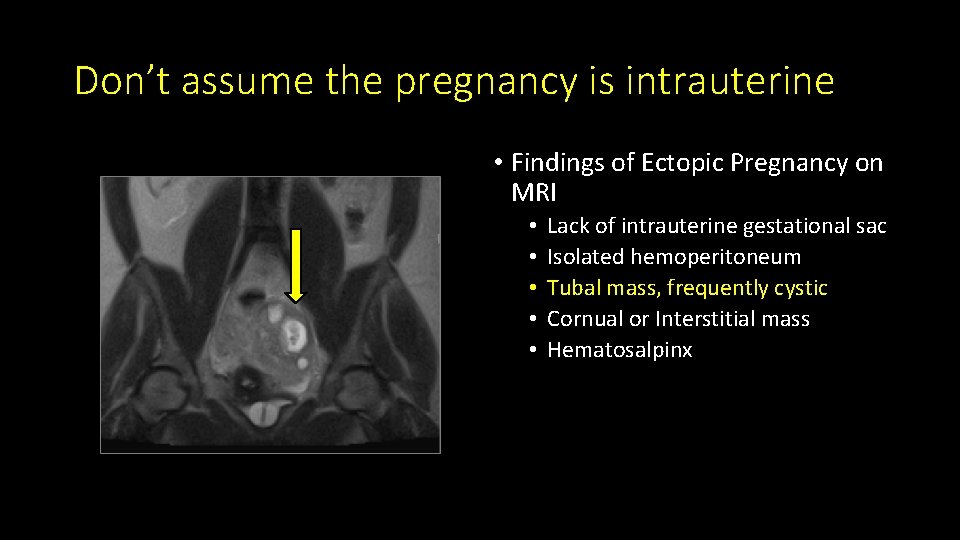

Don’t assume the pregnancy is intrauterine • Findings of Ectopic Pregnancy on MRI • • • Lack of intrauterine gestational sac Isolated hemoperitoneum Tubal mass, frequently cystic Cornual or Interstitial mass Hematosalpinx

Don’t assume the pregnancy is intrauterine • Findings of Ectopic Pregnancy on MRI • • • Lack of intrauterine gestational sac Isolated hemoperitoneum Tubal mass, frequently cystic Cornual or Interstitial mass Hematosalpinx

Don’t assume the pregnancy is intrauterine • Findings of Ectopic Pregnancy on MRI • • • Lack of intrauterine gestational sac Isolated hemoperitoneum Tubal mass, frequently cystic Cornual or Interstitial mass Hematosalpinx

Don’t assume the pregnancy is intrauterine • Findings of Ectopic Pregnancy on MRI • • • Lack of intrauterine gestational sac Isolated hemoperitoneum Tubal mass, frequently cystic Cornual or Interstitial mass Hematosalpinx